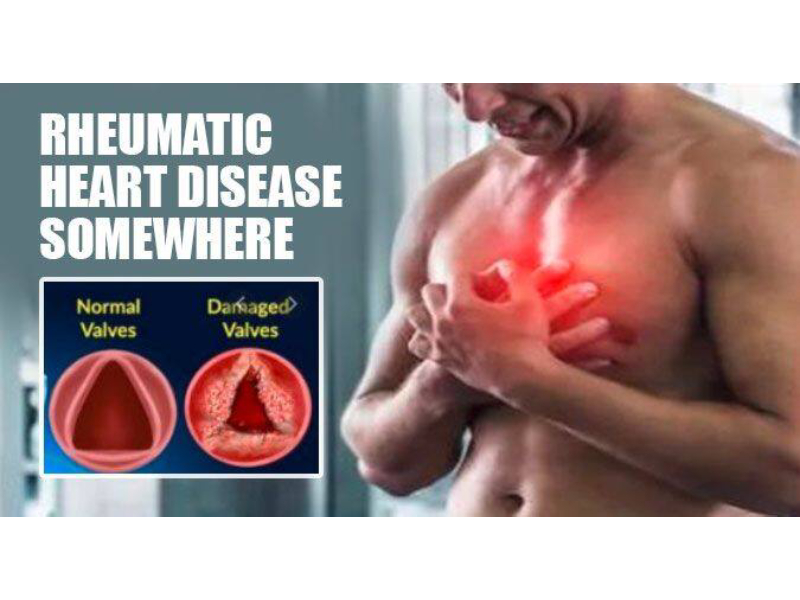

Heart disease is a broad term used to refer to a range of conditions that affect your heart. It includes blood vessel diseases like coronary artery disease, heart rhythm problems or arrhythmias, congenital heart defects and dilated cardiomyopathy among ot